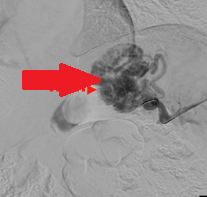

CT Angiography. Presence of a ruptured pseudoaneurysm of the common hepatic artery (Courtesy Dr. V. Penopoulos)